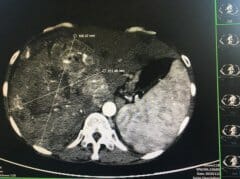

发现感染乙肝病毒后,定期复查的重要性

案例 :一位女性患者,45岁,在去年初就感觉右上腹部不舒服,有时候隐隐作痛,全身稍微有点乏力,自己以为是这几天熬夜、劳累造成的,所以没有在意,就这样坚持了一两个月,感觉右上腹疼痛加重了。她才去医院就诊,经过详细检查,她是一名乙型病毒性肝炎患者...